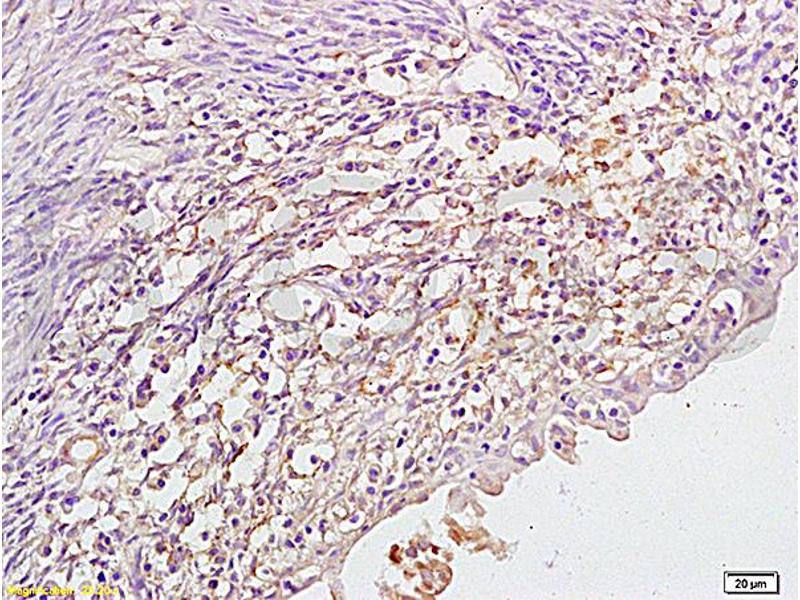

CYP17A1 Reactivité: Humain, Rat WB, IHC, FACS Hôte: Lapin Polyclonal unconjugated

N° du produit ABIN4886555

500,50 €

Plus frais de livraison 40,00 € et TVA

100 μg

Destination: France

Envoi sous 8 à 12 jours ouvrables